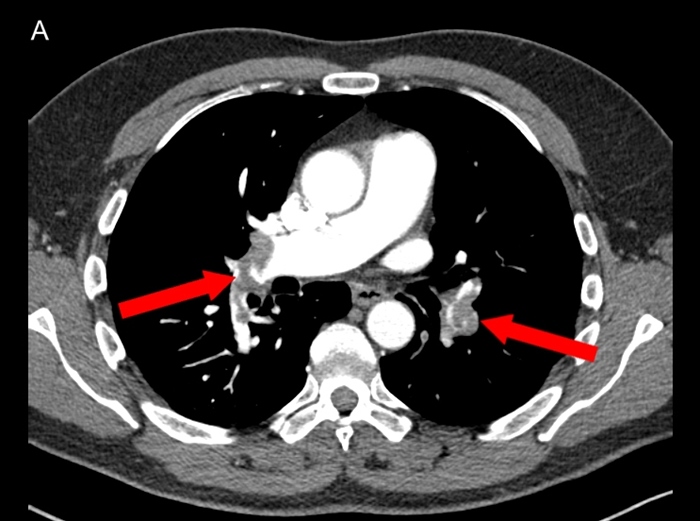

Pulmonary emboli: Approximately 10% of patients with PE have occlusion of a peripheral pulmonary artery by thrombus, causing pulmonary infarction. These small peripheral thrombi are more likely to cause pleuritic chest pain and hemoptysis, due to inflammation and irritation of the lung parenchyma and adjacent visceral and parietal pleura. CT shows wedge shaped lungs and pleural effusion:

contrast CT: pulmonary artery filling defect: